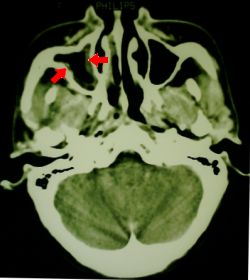

CT scan showing fairly subtle mucosal thickening in the right maxillary sinus. No fluid was present

Fig 1. CT scan showing sinusitis